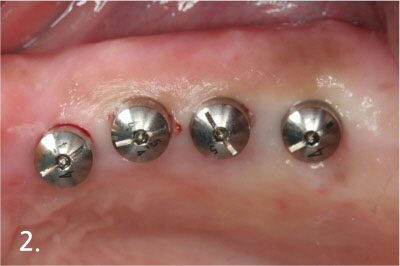

Placing implant for over-denture

Engaging attachment to implant

Engaging attachment inside denture

After engaging attachment with implant and denture. Now, patient can feel comfortable with denture much more than before